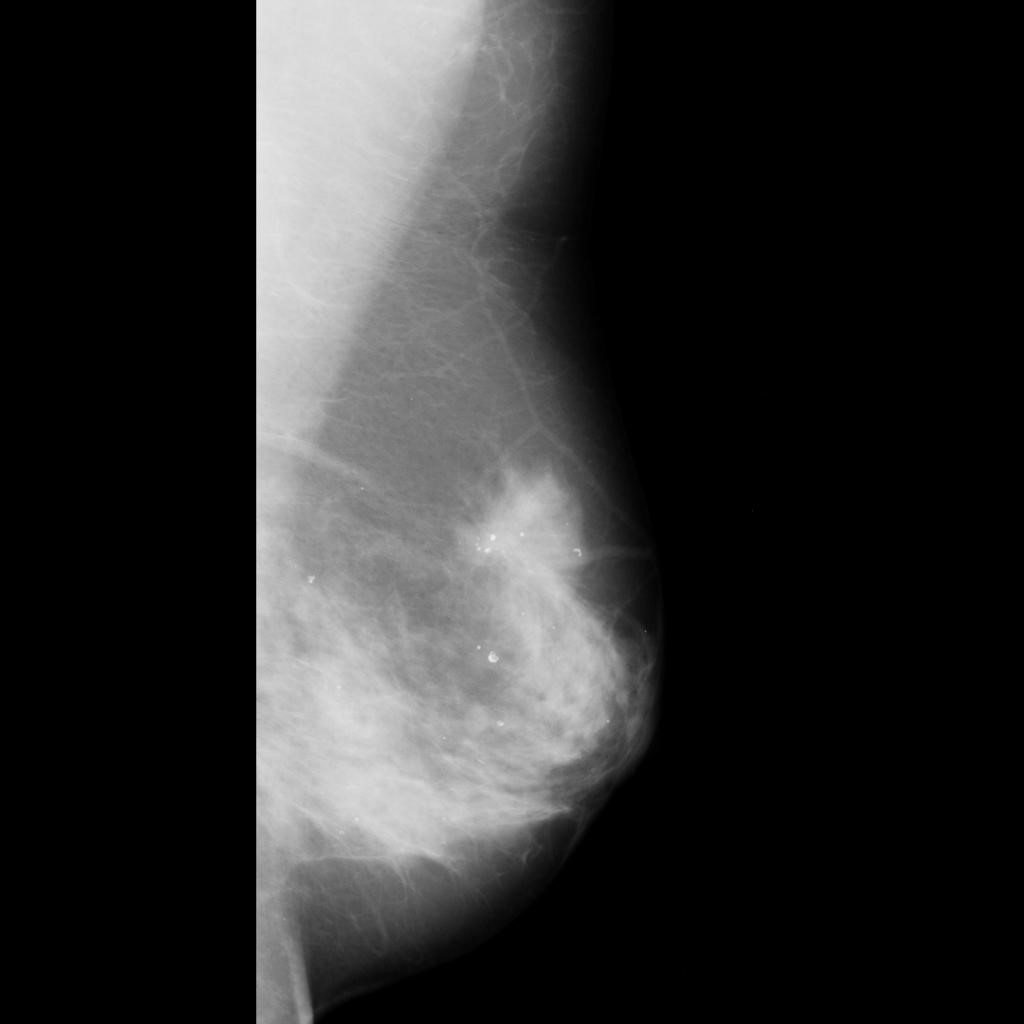

malignant